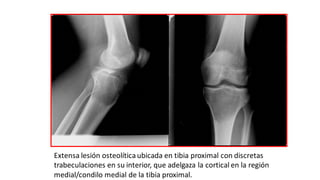

Extensa lesión osteolíticaubicada en tibia proximal con discretas

trabeculaciones en su interior, que adelgaza la cortical en la región

medial/condilo medial de la tibia proximal.